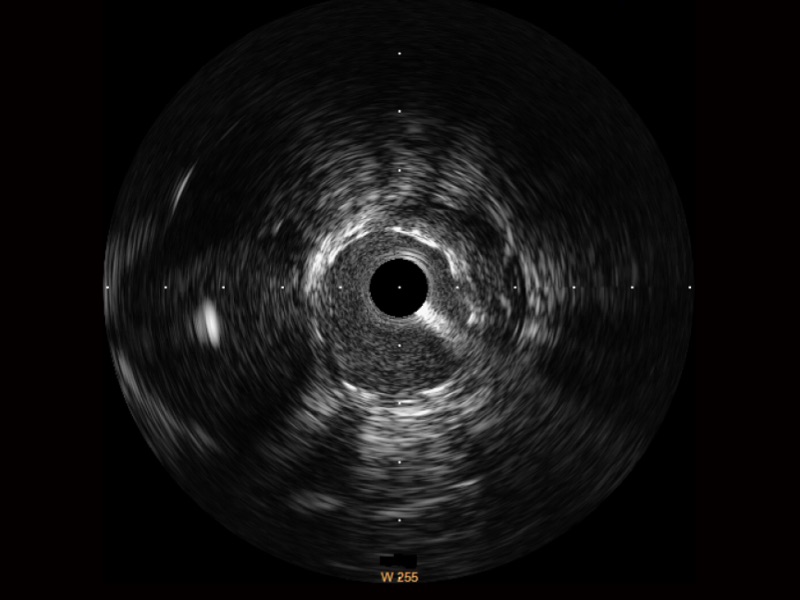

新葡的京集团8814检测站宽频IVUS图像

传统IVUS图像

对比传统IVUS导管成像,新葡的京集团8814检测站宽频IVUS图像的近场支架梁显影更细腻,远场中膜外血管仍清晰可辨,兼顾远中近,兼顾分辨力与穿透深度